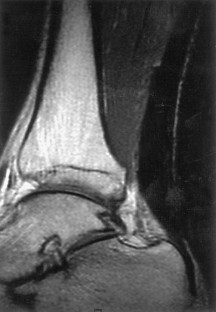

Fig. 2.